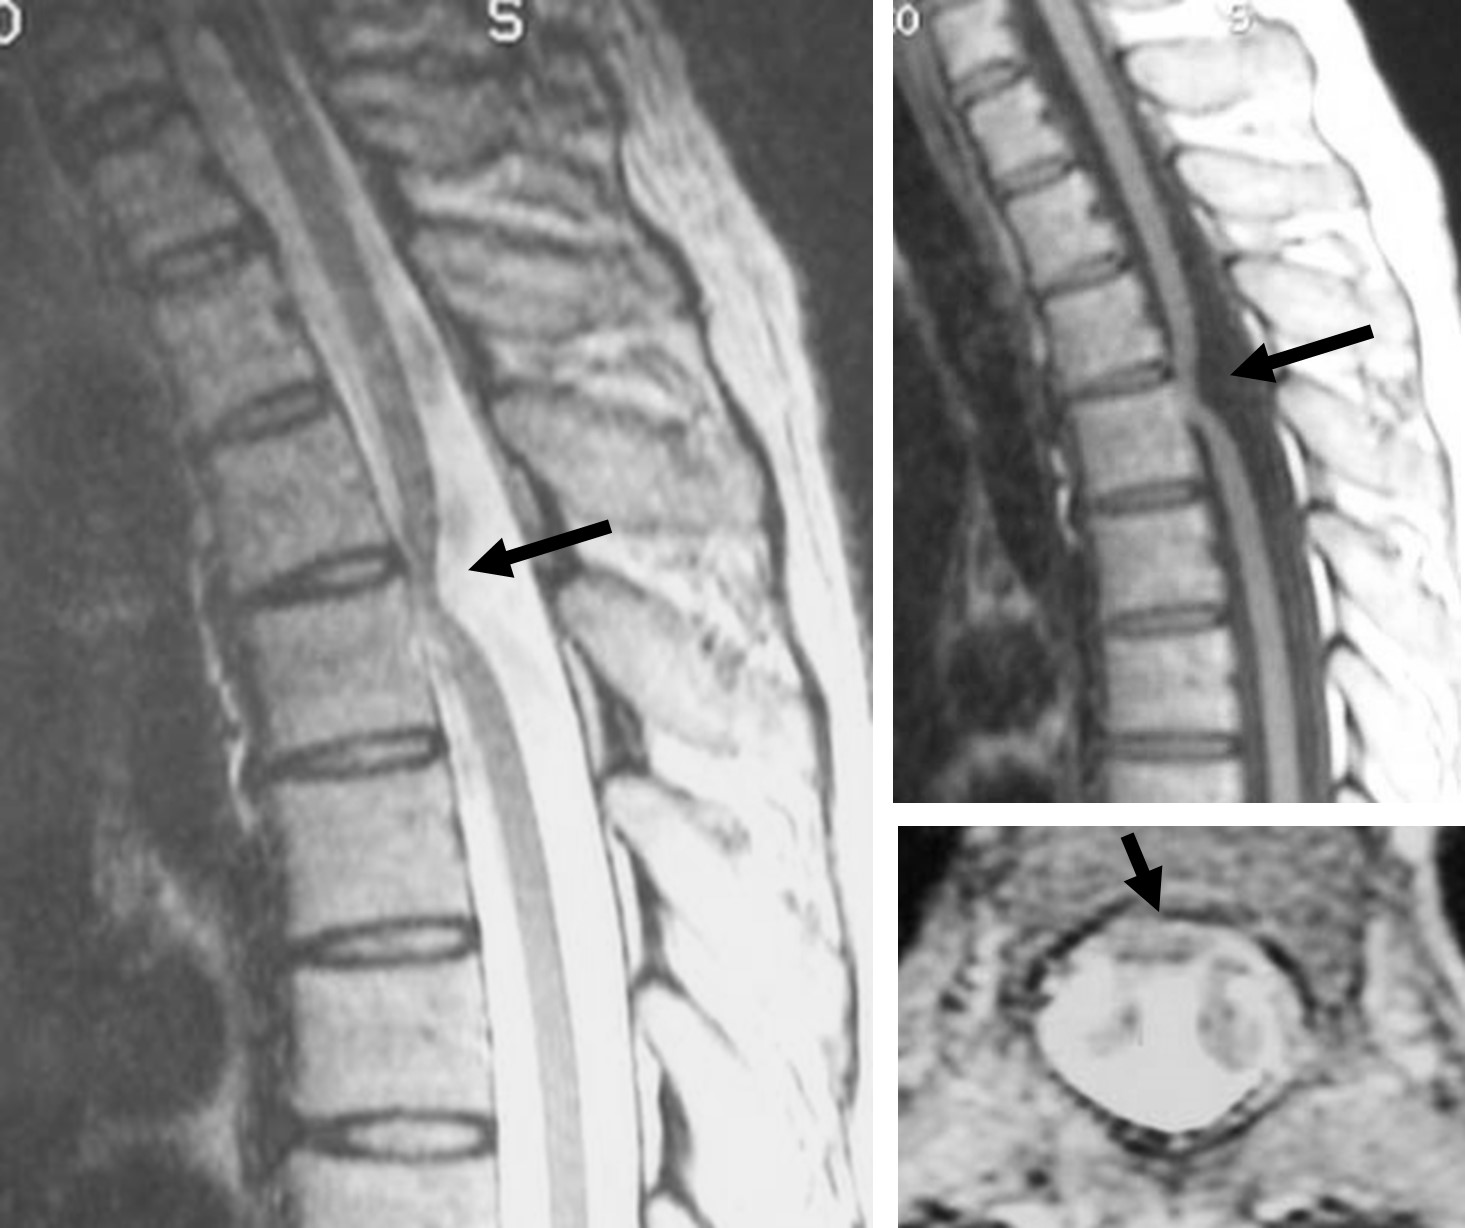

診断はまず病歴と身体検査により行われ、続いてMRIなどの画像検査が用いられます。MRIは特に脊髄ヘルニアの診断に有用で、脊髄の嵌頓を詳細に評価できます。

図 脊髄が欠損した硬膜に嵌頓している(矢印)